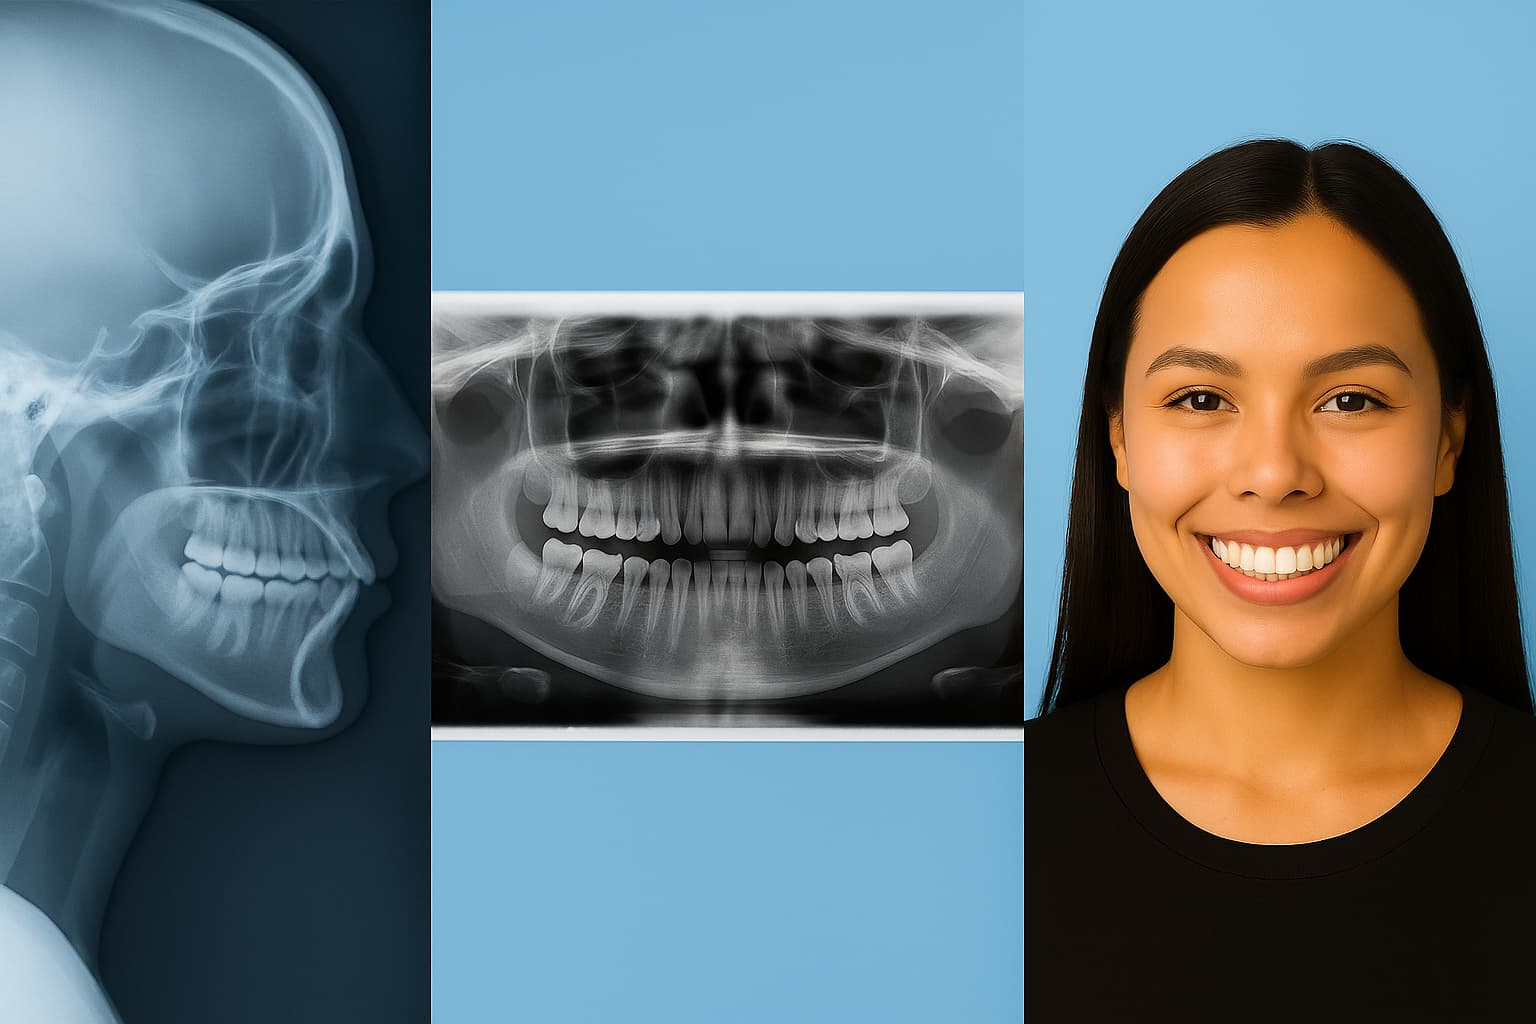

Step 1Complete Orthodontic Records

We take a full set of orthodontic X-rays and high resolution photos to evaluate your bite, alignment, jaw position, and facial symmetry. This is not your average dental exam. This is a comprehensive evaluation of growth and aesthetics.